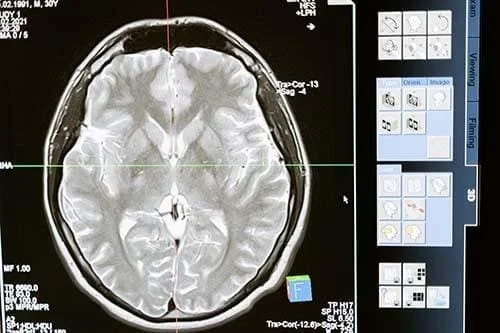

- Brain and Neurological Disorders

- TBI